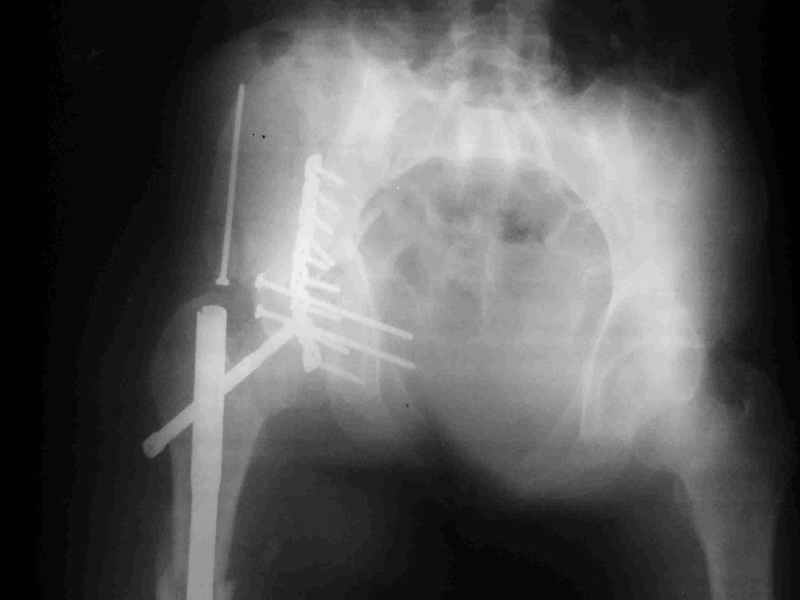

Re: Acetabular fracture

Djoldas kuldjanov, M.D. 02 Сентябрь 2004, 09:05

По снимкам:

Диагноз- перелом с вовлечением таза, разрыв правого сакро-илиак сочленения vertical shear injury, перелом крыла подвздошной кости?, перелом ацетабулум Т type или Both column?, перелом шейки бедра, перелом проксимального отдела бедра.

> Ваш окончательный диагноз?

перелом крыла правой подвздошной кости, перелом обеих колонн вертлужной впадины, двусторонний перелом лонных костей (С2.2) повреждение передних связок правого крестцово-подвздошного сочленения,

ипсилатеральный перелом шейки и диафиза бедра.

К сожалению, набора для ретроградного или антеградного реконструктивного штифтования в операционной нет, поэтому доставка заняла н-ное время. Вопрос, который возник у меня- по поводу оптимальной тактики хирургии: вся фиксация в один этап из расширенного доступа или последовательно сначала бедро и позже реконструкция впадины, комбинированный доступ к впадине отдельно к передней и задней колоннам или из расширенного илеофеморального одного доступа. Все-таки решил остановиться на одноэтапном подходе и спустя 5 дней (как раз и наборы привезли) из расширенного илеофеморального доступа сначала фиксировал реконструктивным штифтом Smith&Nephews бедро и

шейку (благо перелом шейки 2 типа -относительно стабильный) затем фрагмент крыла подвздошной кости Lag screw, далее пластина на заднюю колонну и винты в переднюю колонну.(с размерами и направлением винтов ошибка вышла:-((, но интраоперационно у меня была полная уверенность , что винты *ушли* в лонную кость).

Еще раз спасибо за комментарии и готовность помочь с имплантами. Постоп картинки в приложении,